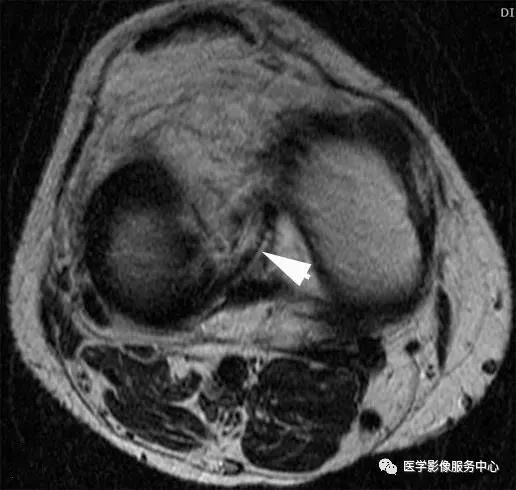

十、假性桶柄样撕裂

常出现在外侧半月板后角的冠状扫描层面上,内侧半月板极少出现此情况。扫描层面同时包括外侧半月板体部及半月板后角,易误诊为桶柄样撕裂,在膝关节外旋时更易出现。结合矢状位相可排除桶柄样撕裂。

A:冠状位MRI,箭头所指为外侧半月板后角,易误诊为桶柄裂;

B:按照图中虚线所示的位置进行MRI扫描时,会出现假性桶柄样撕裂的情况